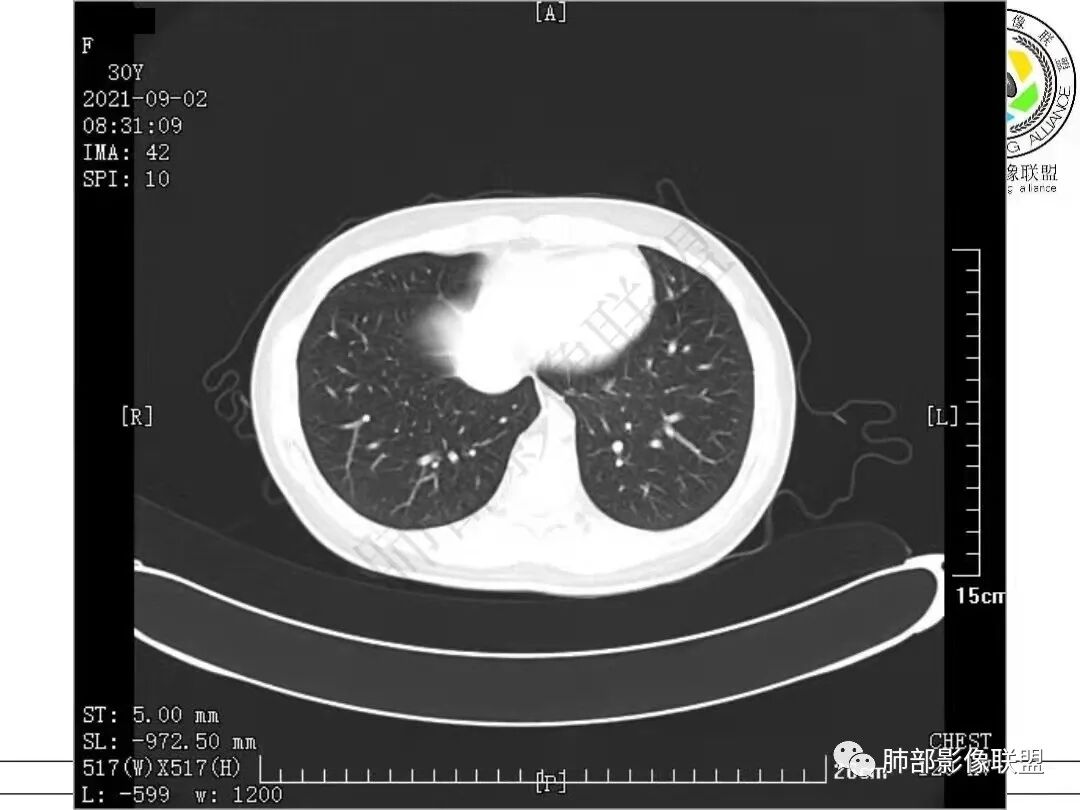

1.病例一:68岁男性,体检发现肺结节,肿瘤标志物CA199、CA50、CEA升高,其中CEA升高显著,超过正常范围的5倍以上。右肺下叶胸膜下结节影,整体较膨隆,部分层面可见锯齿状边缘,边界清晰,周围可见细毛细影,可见血管集束征、胸膜牵拉。密度不均,可见磨玻璃密度区及空泡征,胸膜下脂肪间隙显示不清。增强后显示轻、中度强化。